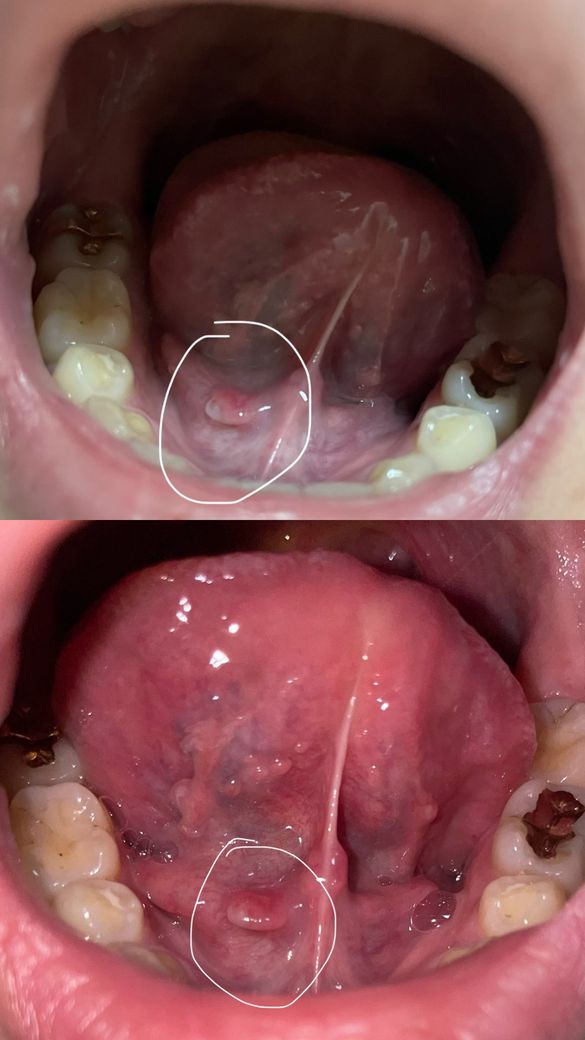

자고 일어났다가 아무 생각 없이 혀 움직이는데

혀 밑에 뭔가 달랑거리면서 튀어나온거 같은게

느껴지길래 거울보니 요런게 생겨 있어요

통증은 하나도 안느껴지고 불편함도 안느껴집니다

• 1번 째 사진

• 사진 위치와 모양을 보면 설하부(혀 밑) 정중선 근처에 작고 매끈한 돌기 형태로, 통증이 없다는 점까지 고려하면 가장 가능성 높은 것은 정상 구조인 설하소구(Wharton관 개구부) 혹은 그 주변 점막이 약간 도드라져 보이는 경우입니다. 개인에 따라 양쪽이 비대칭이거나 한쪽만 더 튀어나와 보일 수 있습니다.

다만 감별로는 초기 점액낭종(침샘관이 일시적으로 막혀 생기는 작은 물집)이나 경미한 자극 후 부종도 가능하지만, 일반적으로는 투명하거나 약간 푸른빛을 띠고 크기가 변하거나 터졌다가 다시 차는 양상을 보입니다. 현재 사진처럼 단단해 보이는 작은 돌기이고 통증, 빠른 크기 증가, 궤양이 없다면 병적 가능성은 낮습니다.

경과 관찰이 원칙이며, 2주에서 3주 이상 크기 변화 없이 지속되거나 점점 커짐, 통증 발생, 출혈, 색 변화(검붉거나 하얗게 궤양화) 중 하나라도 나타나면 구강악안면외과 또는 이비인후과 진료로 확인하는 것이 안전합니다. 지금 상태만으로는 특별한 처치 없이 지켜보셔도 무방한 소견에 가깝습니다.